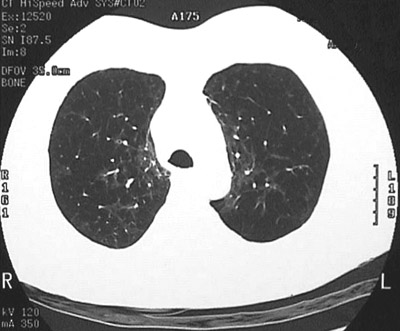

This chest CT scan reveals loculated lucencies in the upper lobes, consistent with centrilobular emphysema.